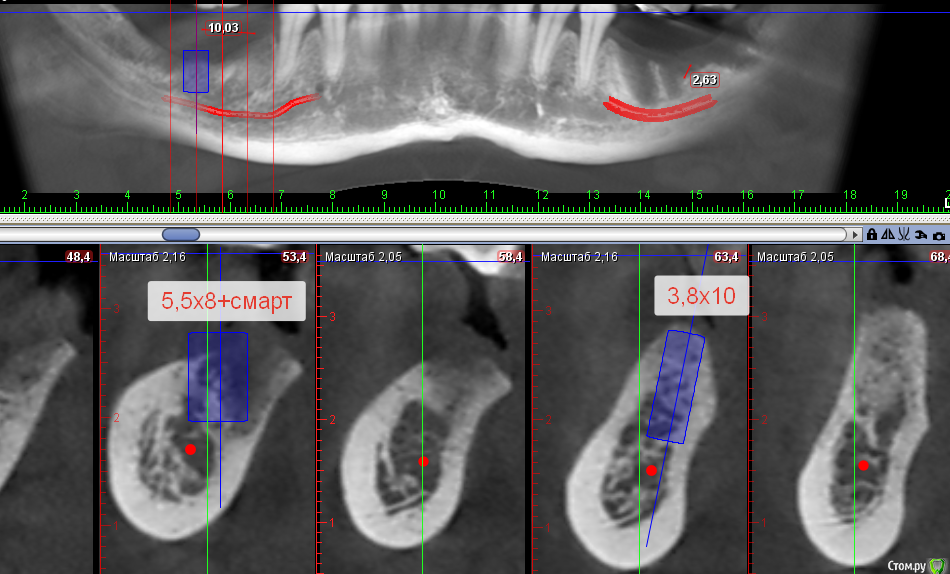

Sergiosse Опубликовано 10 июня, 2017 Поделиться Опубликовано 10 июня, 2017 (изменено) Под сетки "Mega-Oss" и поверх мембраны PRFВ такой ситуации планирую остемовскую сетку ставить .Пара вопросов Что лучше под нее Ауто или микст,насколько выше платформы импланта взять спейсер, ставить фдм или заглушку?После прф не прорезывается сетка ? Изменено 10 июня, 2017 пользователем Sergiosse Ссылка на комментарий